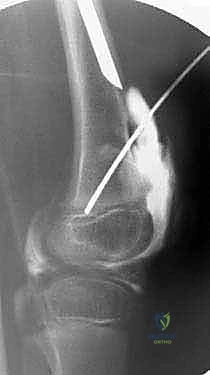

* إصلاح الفخذ الأفحج (Coxa Vara Correction): يقوم الدكتور هطيف بقطع عظمي دقيق في أعلى الفخذ لتعديل الزاوية بين العنق والجسم، وتثبيتها بشرائح ومسامير خاصة بالأطفال. هذا يعيد الشد الطبيعي للعضلات المبعدة ويقضي على العرج.

* تحرير الأنسجة الرخوة: يتم إطالة الأوتار والعضلات المنكمشة التي تعيق حركة المفصل.

2. قطع عظم ديجا (Dega Osteotomy)

في الحالات التي يكون فيها الحق (تويج الحوض) ضحلاً ولا يغطي رأس الفخذ بشكل كافٍ (Hip Dysplasia)، يجري الدكتور هطيف عملية "ديجا". يتم فيها عمل شق في عظام الحوض وثنيه للأسفل لتكوين سقف متين يغطي رأس الفخذ، ثم يتم وضع طعم عظمي لتثبيت الوضع الجديد. هذا الإجراء ضروري لمنع خلع الورك أثناء عملية التطويل اللاحقة.